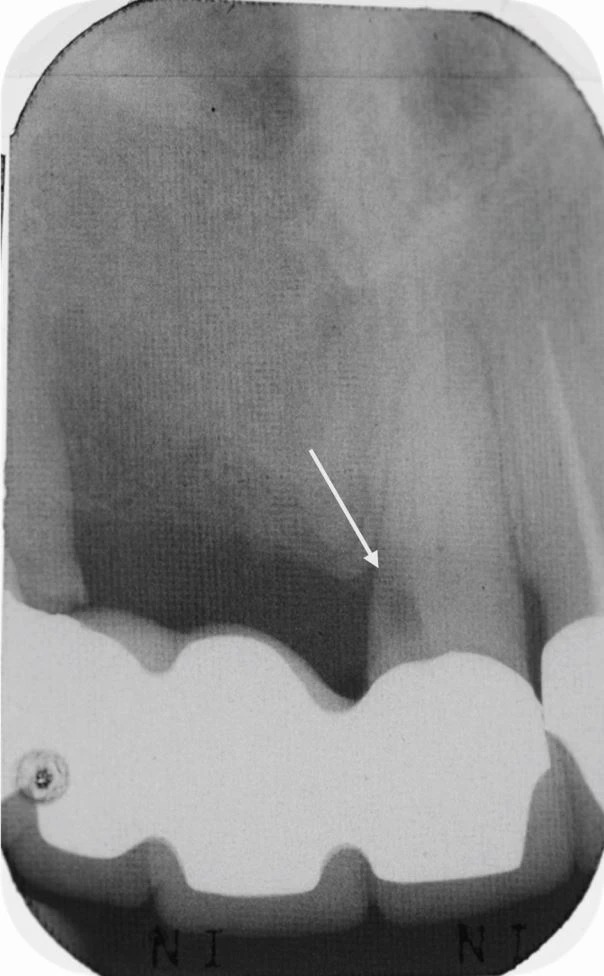

На рисунке 4 в статье показан пример ятрогенной перфорации, возникшей из-за неправильного направления бора при доступе через опорный зуб четырёхзвенного мостовидного протеза. Авторы подчёркивают: потеря анатомических ориентиров при препарировании через реставрации — одна из самых частых причин осложнений.

Зуб 21 утратил жизнеспособность под четырёхзвенным мостовидным протезом, что привело к потере всех анатомических ориентиров. Полость доступа была выполнена с нарушением оси, и в результате возникла ятрогенная перфорация корня. Белая стрелка на изображении указывает на место перфорации.